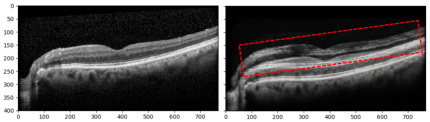

A limitation of our method, although uncommon, is the artifacts that can exist in the predicted image. An example of an artifact is shown in Fig. 7 where the network superimposed duplicate cross-sections on top of each other. This is a weakness of the current GAN methods and represents a potential area for further research. Increasing the training dataset size or constraining the cost function with more priors or implementing a hybrid model of both learning-based and rule-based models may help us solve this problem in the future but this remains, for now, an open problem for neural networks based generative models in medical image analysis.